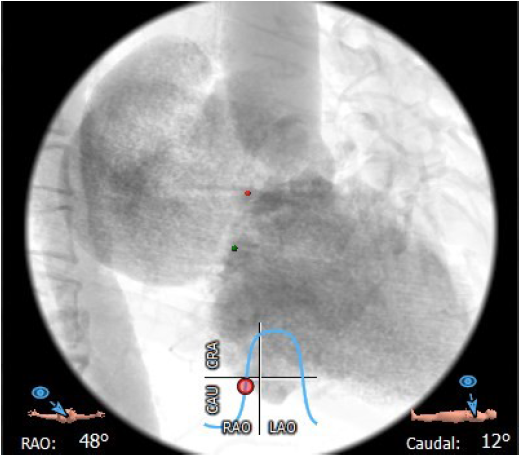

术中影像监护与评估(DSA&TEE)

猪尾导管过瓣环平面进左心房

交换加硬导丝